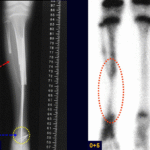

Diagnóstico e tratamento dos tumores músculo-esqueléticos, benignos e malignos primários dos ossos, lesões metastáticas e pseudo tumorais. Prevenção de fraturas em ossos osteoporóticos e patológicos.

Procedimentos cirúrgicos para o diagnóstico e tratamento das lesões neoplásicas do tecido músculo esquelético e reconstruções com próteses e soluções biológicas.

Tratamento ortopédico do aparelho locomotor e das lesões traumáticas. Osteossínteses das fraturas, Reconstruções biológicas ou com próteses de ombro, úmero, cotovelo, quadril, fêmur, joelho e tíbia.